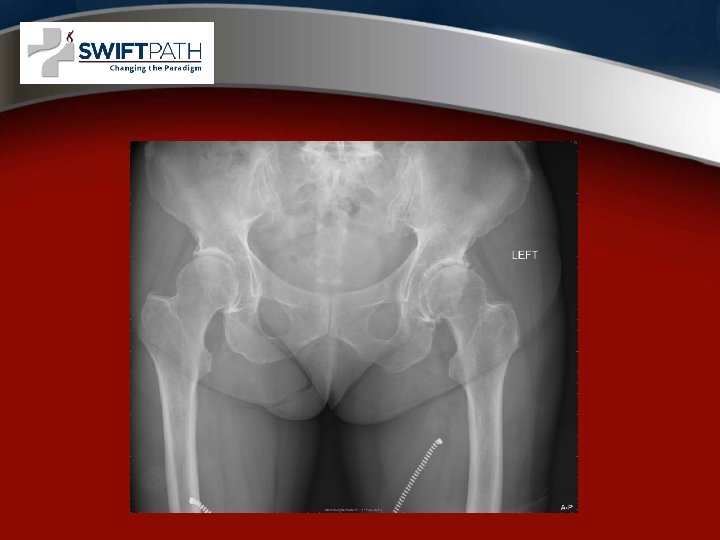

X-ray of a degenerative hip

Hip Arthritis symptoms • Groin and buttock pain with activity then later at rest. • Decreased exercise tolerance with catching and pain. • Limited range of motion.

Surgical options • Arthroscopy for labrum tears • Total hip replacement